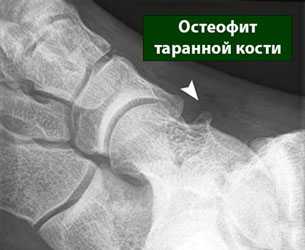

Не смотря на то, что Loomer с соавт. сообщили, что только от 50% до 66% остеохондральных дефектов обнаруживаются при помощи обычной рентгенографии, данный метод является важной отправной точкой и может быть полезен для исключения другой патологии голеностопного сустава [20]. Рентгенологическое исследование голеностопного сустава должно включать переднюю, заднюю и в 3⁄4 внутренней ротации проекции. Все проекции выполняются стоя (под нагрузкой) и называются функциональными. Функциональные рентгенограммы могут быть полезны для выявления сопутствующей нестабильности голеностопного сустава, проекция 3⁄4 во внутренней ротации, помогает в визуализации щели межберцового синдесмоза, а так же отображает передне-внутрений импижмент (таранной и большеберцовой кости) в случае его наличия. Выполненные в положении подошвенного сгибания прямая и 3⁄4 проекция во внутренней ротации могут быть полезны в выявлении заднемедиального поражения таранной кости. Рентгенологические признаки, которые могут быть определены, варьируются от небольших участков сдавления субхондральной кости до крупных отслоенных остеохондральных фрагментов. Радиографическая

система классификации была разработана Berndt и Harty в 1959 году и остается золотым стандартом. (Табл. 1) [16]. Loomer с соавторами дополнили имеющуюся классификацию, на основе не только рентгенограмм, а также МРТ (магнитно-резонансная томография) и КТ (компьютерная томография), и добавили стадию V в систему классификации Berndt и Harty [22].